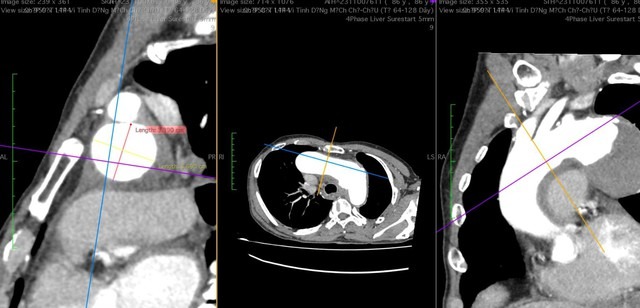

Sau khi thăm khám, làm các xét nghiệm cận lâm sàng và chụp MSCT, bệnh nhân được chẩn đoán phình lớn động mạch chủ ngực ngay dưới động mạch dưới đòn trái, kích thước 57 x 59mm, khối phình gây triệu chứng đau ngực và khàn tiếng do liệt dây thần kinh quặt ngược trái.

TS.BS Lê Thế Anh - Trưởng khoa Nội Tim mạch, người trực tiếp can thiệp và điều trị cho bệnh nhân D. cho biết, trường hợp bệnh nhân này là ca bệnh rất phức tạp, ngoài kích thước khối phình lớn có nguy cơ vỡ bất cứ lúc nào ảnh hưởng đến tính mạng người bệnh.

"Vị trí và đặc điểm của túi phình đặc biệt, cổ túi phình rất ngắn (1cm), không phù hợp với chỉ định đặt stent bằng phương pháp can thiệp thông thường do có thể sẽ làm bít tắc đến các mạch máu chính nuôi não và cánh tay. Bên cạnh đó, bệnh nhân tuổi cao, thể trạng yếu nên phương pháp phẫu thuật cũng không được chỉ định", TS.BS Lê Thế Anh nói.

Theo TS.BS Lê Thế Anh, đây là một trường hợp phẫu thuật mạch máu rất phức tạp, đặc biệt là khi phải chuyển vị hoàn toàn 2 nhánh mạch máu nuôi não. Trong suốt quá trình phẫu thuật chuyển vị phải duy trì huyết động tối ưu, đảm bảo độ mê và theo dõi tưới máu não liên tục bằng máy theo dõi độ bão hòa oxy não để đảm bảo cung cấp máu đầy đủ cho não bệnh nhân.

Bên cạnh đó, vị trí túi phình là vị trí khó để đặt stent graft do liên quan đến giải phẫu vùng cổ, có thể gây tổn thương thần kinh đặc biệt vùng tủy ngực. Tuy nhiên, nhờ việc phối hợp nhịp nhàng liên chuyên khoa trong điều trị, bệnh nhân đã được điều trị thành công. Đây không chỉ là niềm vui cho bệnh nhân và gia đình mà còn là niềm vui của đội ngũ y bác sĩ.